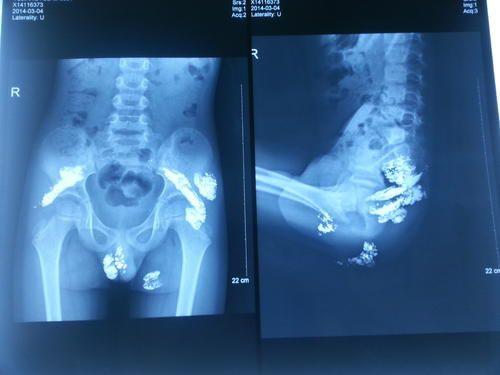

毒物导致中毒的途径通常有三种,即通过呼吸道、消化道或皮肤黏膜吸收。金属汞主要以蒸气的形式经呼吸道吸收,是金属汞中毒的主要途径。而金属汞经完整的黏膜及皮肤吸收极少。因而误服水银无需洗胃,可行腹部X线平片检查确定确有摄入。轻度导泄或进食粗纤维食物促进排出体外即可。